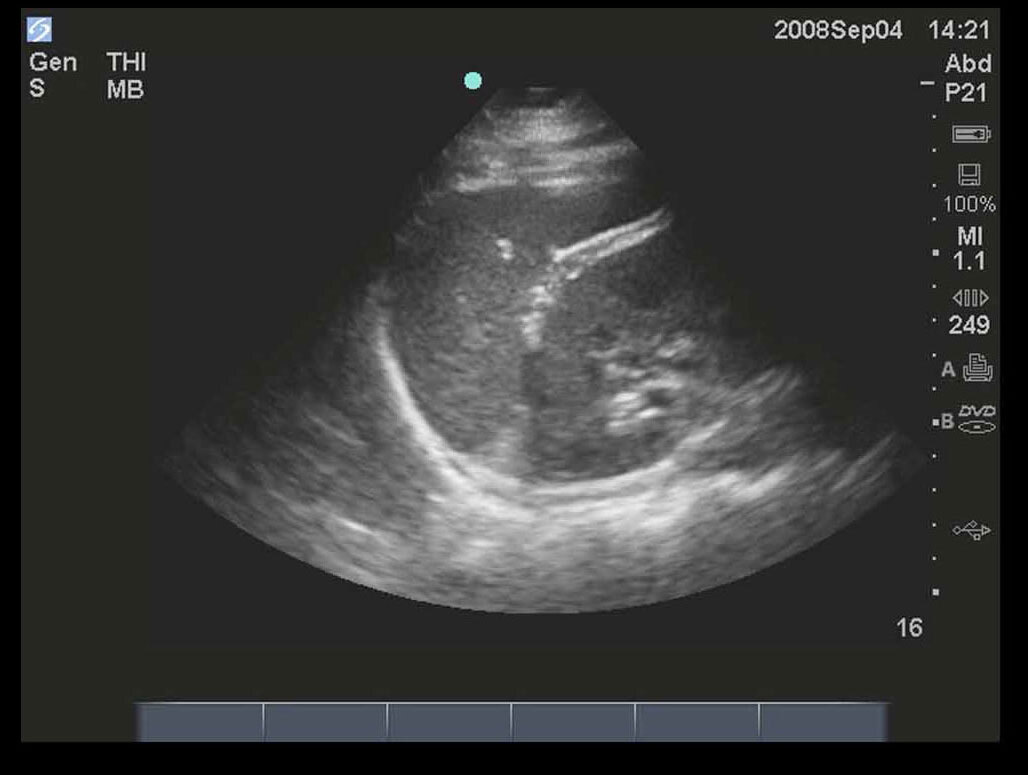

FAST Left Upper Quadrant (LUQ) 1 Image

M-Turbo: FAST Exam, Left Upper Quadrant 1.